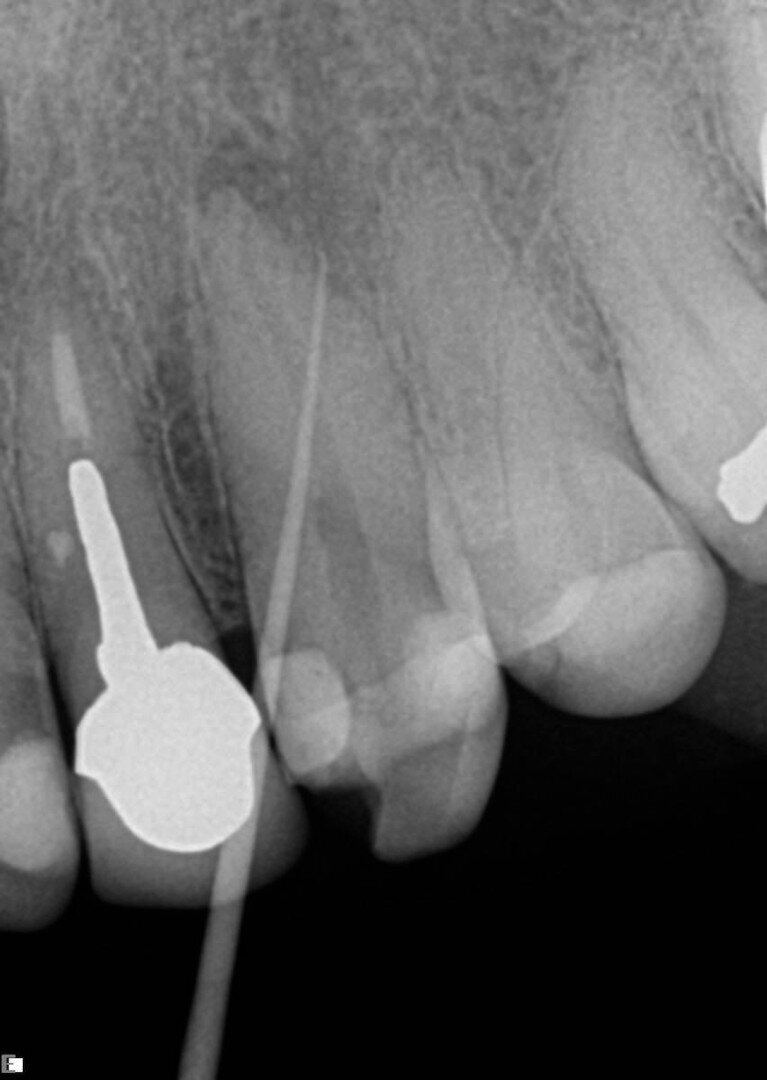

Drugi maksilarni molari su po mom mišljenju jedan od najzahtevnijih zuba za endodontsko lečenje zbog svog položaja i nepredvidive anatomije. U ovom primeru, pacijent je upućen zbog ireverzibilnog pulpitisa (Sl. 5). Gledajući preoperativni rendgenski snimak, možemo uočiti zakrivljenost posebno mezijalnih i palatinalnih kanala korena. Korišćena sekvenca je kao što je ranije opisano, počevši od otvarača 25/0.08 koliko god ide i to do tik iznad krivine, nakon čega sledi K-File 8 za određivanje radne dužine i 13/0.06 Traverse file koji se koristi za određivanje radne dužine u svim kanalima. Tokom korišćenja Traverse turpije 13/0.06 nisam osetio veliki otpor, pa sam odlučio da nastavim sa sekvencom konusa od 0.06. Sledeća turpija je bila 20/0.06 ZenFlex, a zatim 25/0.06 takođe ZenFlex. Lično, verujem u apikalno proširenje, i iz tog razloga sam koristio i ZenFlex  file 30/0.04 kao konačnu turpiju za proširenjee u ovom slučaju. Koristio sam srednji konus kao glavni i postigao 3D opturaciju sistema (Sl. 6). Naravno, izvršio sam kompletnu hemijsku pripremu, po svom redosledu, tokom postupka.